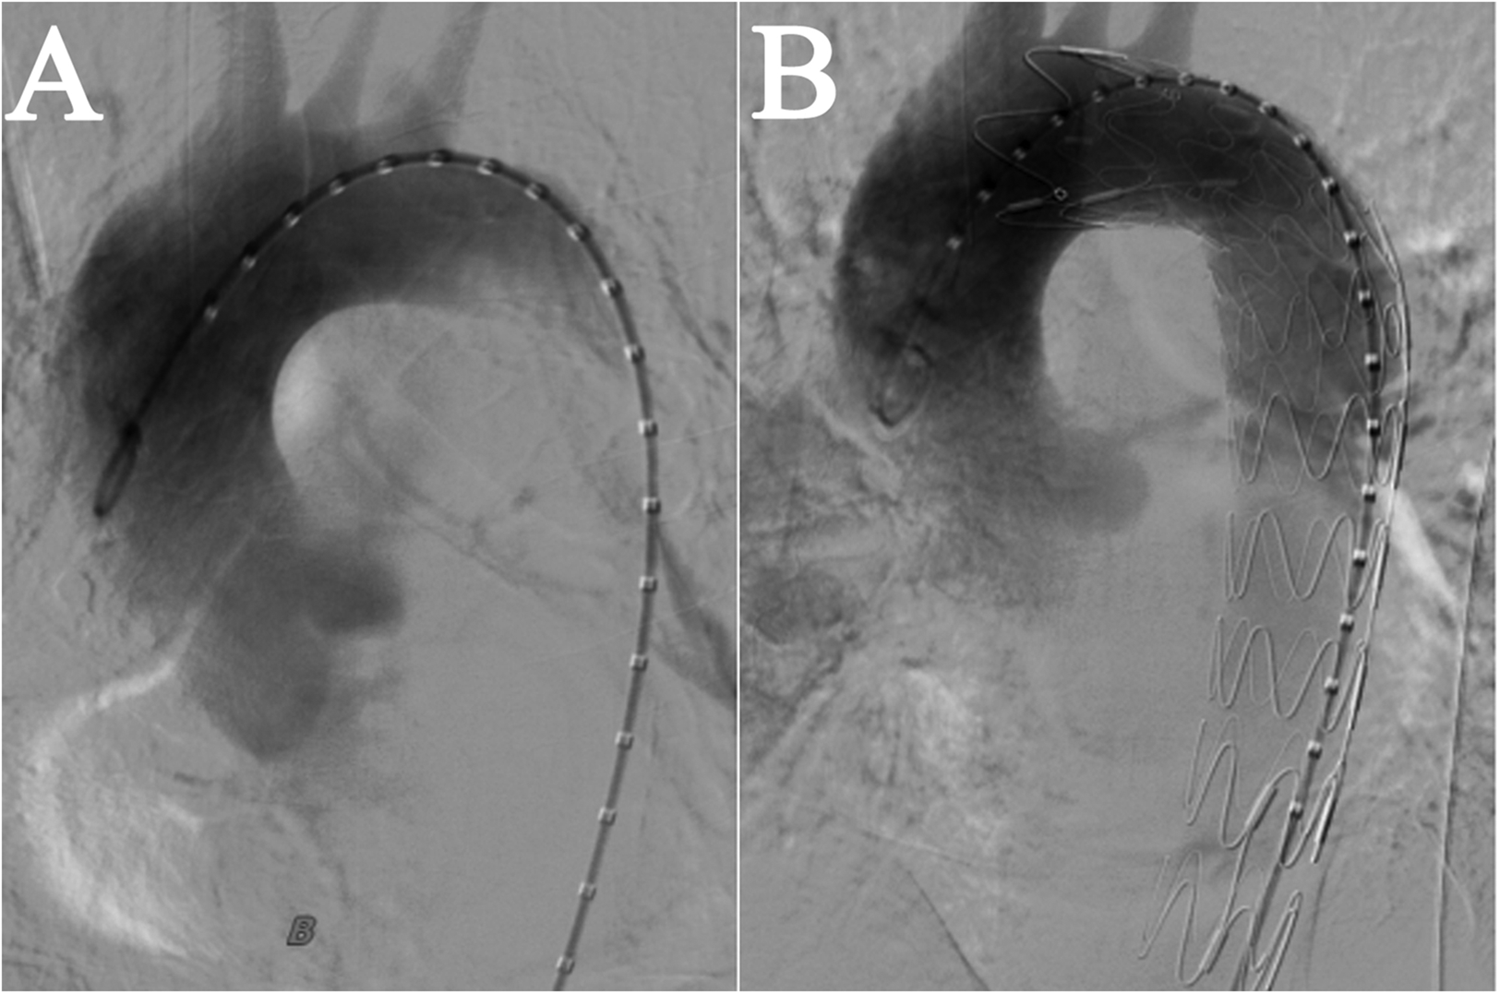

We performed an emergency TEVAR procedure on the patient under general anesthesia. The angiogram revealed a localized rupture in the thoracic aorta located approximately 6 mm distal to the left subclavian artery, with evident massive contrast extravasation. The proximal end of the stent graft was positioned in the distal third of the left subclavian artery. The deployment proceeded smoothly, and the stent graft achieved a satisfactory morphological appearance. A subsequent aortic angiogram confirmed that the thoracic stent graft had good wall apposition, with no evidence of endoleak, and the aortic rupture was successfully excluded. Blood flow to the left subclavian artery remained well preserved, obviating the need for a carotid-subclavian bypass procedure (Figure 2). The spinal cord protection strategy employed throughout the procedure involved maintaining the mean arterial pressure above 65 mmHg.

Figure 2

Intraoperative imaging in TEVAR. (A) Prior to Stent Implantation. (B) After stent implantation, blood flow in the left subclavian artery was normal, with no evidence of leakage from the aorta.